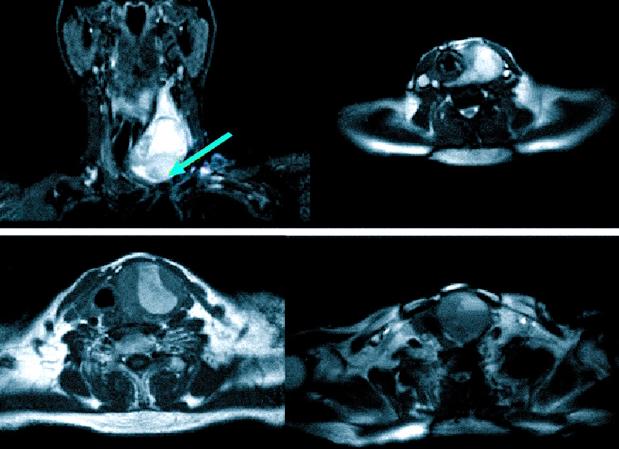

Магнитнорезонансная томография щитовидной железы является современным методом диагностики, основанном на явлении ядерного магнитного резонанса. С его помощью можно получить объемное или пошаговое изображение. МРТ щитовидной железы показывает состояние опухоли, ее капсулу и расположение относительно других близлежащих органов.

Различные опухоли лучше всего диагностируются при помощи резонансной томографии щитовидной железы. Для определения размеров и вида опухоли достаточно компьютерной томографии щитовидной железы, а влияние ее на соседние органы, наличие метастазов в лимфоузлах возможно увидеть только при помощи МРТ щитовидки.

Во время исследования визуально оцениваются размеры, структура и форма органа. В основном использование данного метода дает возможность исследования распространенности увеличенной железы в грудную клетку при выявлении загрудинного зоба. Обследование проводится при недостаточности данных, полученных с помощью УЗИ. МРТ выявляет увеличенные лимфатические узлы в грудной полости, а также позволяет обнаружить сдавливание щитовидной железой окружающих тканей. При наличии злокачественных опухолей исследование этим способом дает информацию о взаимном расположении органов шеи.

Диагностика МРТ позволяет различать объемные образования размером до 1 мм. Врач оценивает контуры капсулы, ее взаимодействие с рядом расположенными тканями, что важно для выбора метода терапии.

Во время диагностики специалист получает трехмерную картинку, где видны изменения в пораженных тканях и органах. Он оценивает полученные данные по окончании сканирования и сохраняет их на цифровых носителях. Такая информация важна при лечении для контроля над состоянием пациента.